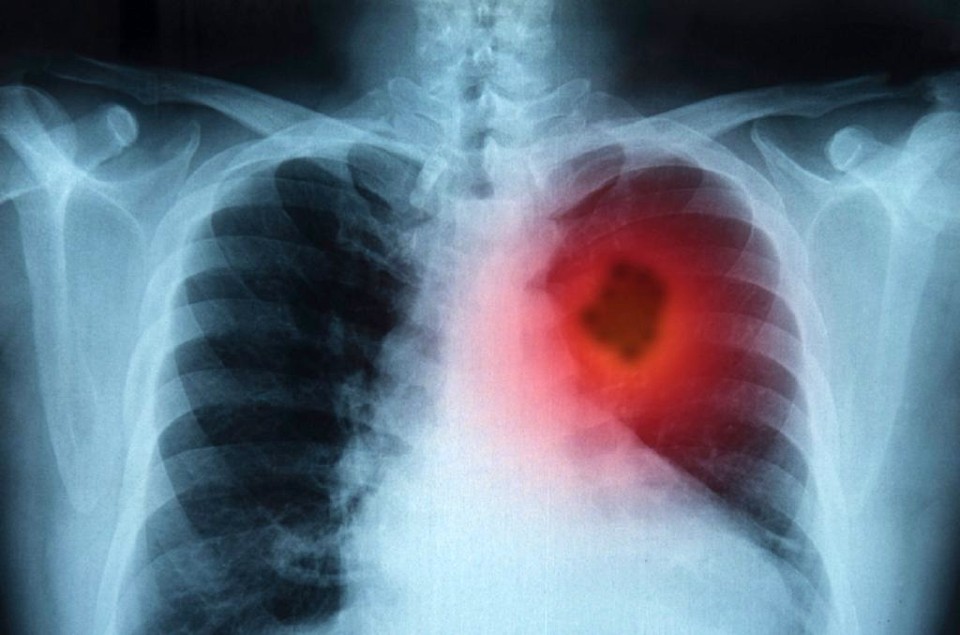

He found out a few years ago that he suffers from lung cancer. When he got to the doctor, his condition was very serious, so the doctors told him he had no chance. However, the man did not give up and cured himself of cancer.

Ante Kresich found out a few years ago that he suffers from lung cancer. When he got to the doctor, his condition was very serious, so the doctors told him he had no chance. However, the man did not give up and cured himself of cancer. Look what he did!